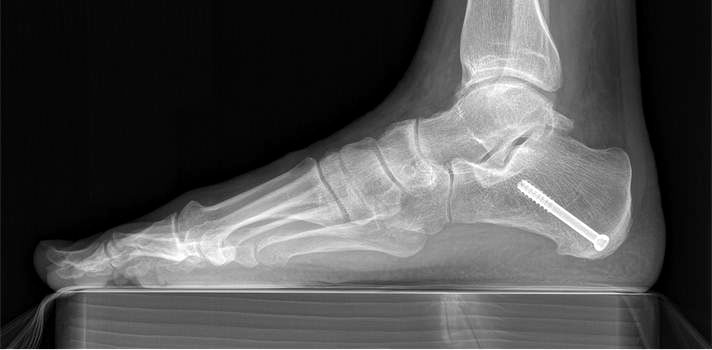

Operationstechnik

715.<br> Für die medialisierende Calcaneusosteotomie wird ein bogenförmiger Hautschnitt in Höhe des hinteren Fersenbeines gesetzt, die Subcutis bis zum Fersenbein durchtrennt und dieser bogenförmige Lappen nach ventral präpariert. Dadurch kommt es zu einem Schutz des Nervus suralis, welcher gemeinsam mit den Peronealsehnen nach vorne gehalten wird.<br> Es wird nun das Fersenbein mit einem Wundspreizer eingestellt und cranial sowie caudal mit 2 Hohmannhaken umfahren.<br> Dann wird das Fersenbein mit der oszillierenden Säge osteotomiert, mit dem Meißel und dem Wundspreizer distrahiert.<br> Danach wird das Fersenbein ca. 1 cm nach medial verschoben, unter Vermeidung der Cranialisierung des hinteren Calcaneus . Dann wird von dorsal über eine Hautstichincision der Bohrdraht für die 4,5mm (- 6,5 mm) kanülierte Schraube eingebracht und über die Osteotomie in den vorderen Calcaneusanteil vorgeschoben.<br> Kontrolle im Bildwandler in 2 Ebenen. Wenn die Bohrdrahtlage gut ist Überbohren für die kanülierten Schrauben und Eindrehen der Schraube. (Alternativ kann an Stelle der Schraubentechnik auch eine Fixation mit Stufenplatten oder Ähnlichem verwendet werden).<br> Wundverschluss am lateralen Zugang und über der Stichincision.</p>"> 715.<br> Für die medialisierende Calcaneusosteotomie wird ein bogenförmiger Hautschnitt in Höhe des hinteren Fersenbeines gesetzt, die Subcutis bis zum Fersenbein durchtrennt und dieser bogenförmige Lappen nach ventral präpariert. Dadurch kommt es zu einem Schutz des Nervus suralis, welcher gemeinsam mit den Peronealsehnen nach vorne gehalten wird.<br> Es wird nun das Fersenbein mit einem Wundspreizer eingestellt und cranial sowie caudal mit 2 Hohmannhaken umfahren.<br> Dann wird das Fersenbein mit der oszillierenden Säge osteotomiert, mit dem Meißel und dem Wundspreizer distrahiert.<br> Danach wird das Fersenbein ca. 1 cm nach medial verschoben, unter Vermeidung der Cranialisierung des hinteren Calcaneus . Dann wird von dorsal über eine Hautstichincision der Bohrdraht für die 4,5mm (- 6,5 mm) kanülierte Schraube eingebracht und über die Osteotomie in den vorderen Calcaneusanteil vorgeschoben.<br> Kontrolle im Bildwandler in 2 Ebenen. Wenn die Bohrdrahtlage gut ist Überbohren für die kanülierten Schrauben und Eindrehen der Schraube. (Alternativ kann an Stelle der Schraubentechnik auch eine Fixation mit Stufenplatten oder Ähnlichem verwendet werden).<br> Wundverschluss am lateralen Zugang und über der Stichincision.</p>" srcset="/assets/images/a/3-raswd6qgkh6s353.jpg 1x, /assets/images/g/3-exngvjjv83x827d.jpg 1.5x, /assets/images/w/3-836r57qt8j3eh0w.jpg 2x" width="270" height="240" loading="lazy">

Abbildung 3

Abbildung 4

Es wurden insgesamt 16 Patienten nach dieser Methode operiert, sie erhielten alle das oben genannte postoperative Regime. Der durchschnittliche Nachuntersuchungszeitraum betrug 15 Monate (10-31 Monate), das Patientenalter betrug im Durchschnitt 54 Jahre (48-75 Jahre), das Geschlechtsverhältnis männlich : weiblich betrug 3 : 13. Das durchschnittliche Körpergewicht der Patienten betrug 84kg (66-98 kg). Die Auswertung erfolgte durch die VAS und den AOFAS Score, sowie an Hand der Zufriedenheit der Patienten. Desweiteren wurden die radiologischen Parameter (lateraler talonavicularer Winkel, Saltzmann-Aufnahme und talonavicularer Überdeckungswinkel) prä- und postoperativ ausgewertet sowie die Komplikationen analysiert.

Es konnte, bei präoperativer Unfähigkeit zum einbeinigen Zehenspitzenstand, beim letzten Follow up in 62% der Fälle ein schmerzloser einbeiniger Zehenspitzenstand erreicht werden. Der Saltzmann-Winkel konnte von präoperativ 11° (7-17°) auf 3° (1-8°) korrigiert werden. Der seitliche Metatarsale I Winkel wurde von 18° präoperativ (13-23°) auf 7° (5-13°) postoperativ korrigiert. Der talonaviculare Überdeckungswinkel konnte von präoperativ 10° (4-18°) auf postoperativ 7° (2-15°) reduziert werden.